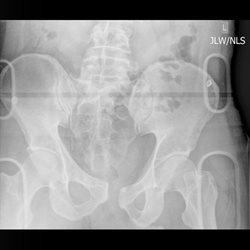

Pelvic Ring Injury 2

Radiograph and CT of same patient.